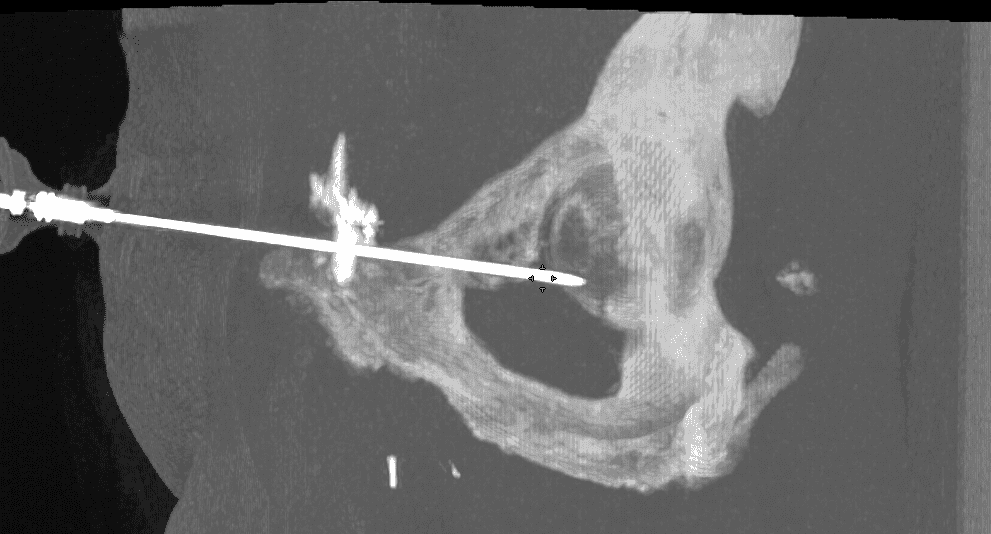

Insertion et déploiement du matériel d’ostéosynthèse :

Une fois l’aiguille positionnée, le vissage est réalisé en respectant la trajectoire prédéfinie, permettant de réaligner les fragments osseux.

Le vissage est ensuite fixé de manière à assurer une stabilité mécanique suffisante pour supporter les contraintes de la zone cotyloïdienne.

Un contrôle scanner final permet de vérifier la position du vissage et la qualité de la réduction anatomique, garantissant ainsi le succès de l’intervention.